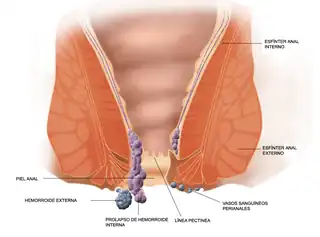

Tipos y localización frecuente de las hemorroides. | ||

Las hemorroides patológicas se dividen en internas, si se encuentran por arriba de la línea pectínea o dentada del conducto anal, y externas las que se encuentran distales o por abajo de la línea dentada. Las hemorroides internas se clasifican en cuatro grados.

Las hemorroides externas, se encuentran recubiertas por piel y pueden trombosarse. En cambio las hemorroides internas se originan desde el plexo hemorroidal superior y están cubiertas por mucosa proximal a la línea dentada. Pueden presentar rectorragia, protrusión, quemazón, prurito, dolor (al presentar alguna complicación) y descarga mucosa.